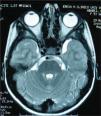

Se presenta el caso de una niña de 5 años y medio, de origen rumano, que en los últimos 4 meses presenta telarquia progresiva y aceleración marcada del crecimiento (velocidad de crecimiento anual de 8cm). La menarquia de la madre tuvo lugar a los 11 años. A la exploración clínica se aprecia un aspecto macrosómico, peso de 30kg (muy por encima de p97) y talla de 126cm (muy por encima de p97). Se objetivan telarquia y pubarquia en estadio 2. El estudio del desarrollo esquelético muestra una aceleración del mismo (edad ósea de 7 años) y la ecografía abdominal, unos ovarios grandes con folículos en su interior; sin embargo, el útero parece prepuberal. Los resultados hormonales basales estarían dentro de la normalidad para la edad: hormona foliculoestimulante (FSH), 2,82 mUI/ml; hormona luteinizante (LH), 0,1 mUI/ml; estradiol, 5pg/ml, y progesterona, 0,23ng/ml. En la RM cerebral se observa un pequeño quiste aracnoideo en la fosa cerebral media izquierda de unos 2cm de diámetro y ningún otro hallazgo patológico (fig. 1).

Los quistes aracnoideos constituyen el 1 % de las masas intracraneales; generalmente son anomalías congénitas causadas por la acumulación de líquido cefalorraquídeo en estructuras quísticas formadas entre dos capas de aracnoides2. La mayoría son clínicamente silentes y se identifican de forma incidental. No obstante, los de localización supraselar se han relacionado, en una frecuencia variable, con la aparición de disfunciones endocrinas múltiples, entre las que figuraría la pubertad precoz en el 2,5% de casos1–6. Varias hipótesis han pretendido explicar el mecanismo de aparición de esta alteración, probablemente en los de mayor tamaño, la compresión del hipotálamo posterior, dejando el anterior intacto, libre de influencias inhibitorias, daría lugar a una activación precoz del eje hipotálamo-hipofisario-gonadal2,4. La región preóptica tendría un papel importante en la regulación de la liberación de hormonas gonadotrópicas desde el lóbulo anterior de la hipófisis4. La evolución de los quistes aracnoideos es incierta y su seguimiento o tratamiento quirúrgico dependerá de su localización, de su tamaño, de los síntomas neurológicos y de la existencia de anomalías asociadas.